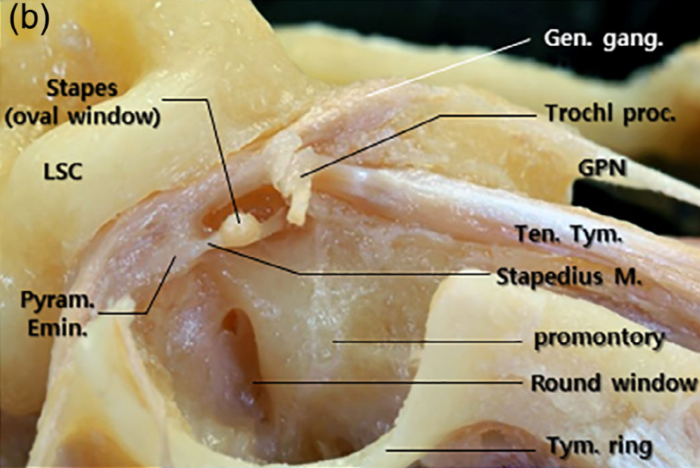

- Podział nerwu twarzowego na segmenty ze szczegółowym opisem ich topografii (przy okazji sporo będzie informacji na temat budowy ucha)

- Jakie gałęzie odchodzą lub dochodzą do nerwu twarzowego w poszczególnych segmentach

- Podział nerwu twarzowego na segmenty ze szczegółowym opisem ich topografii (przy okazji sporo będzie informacji na temat budowy ucha)

- Jakie gałęzie odchodzą lub dochodzą do nerwu twarzowego w poszczególnych segmentach